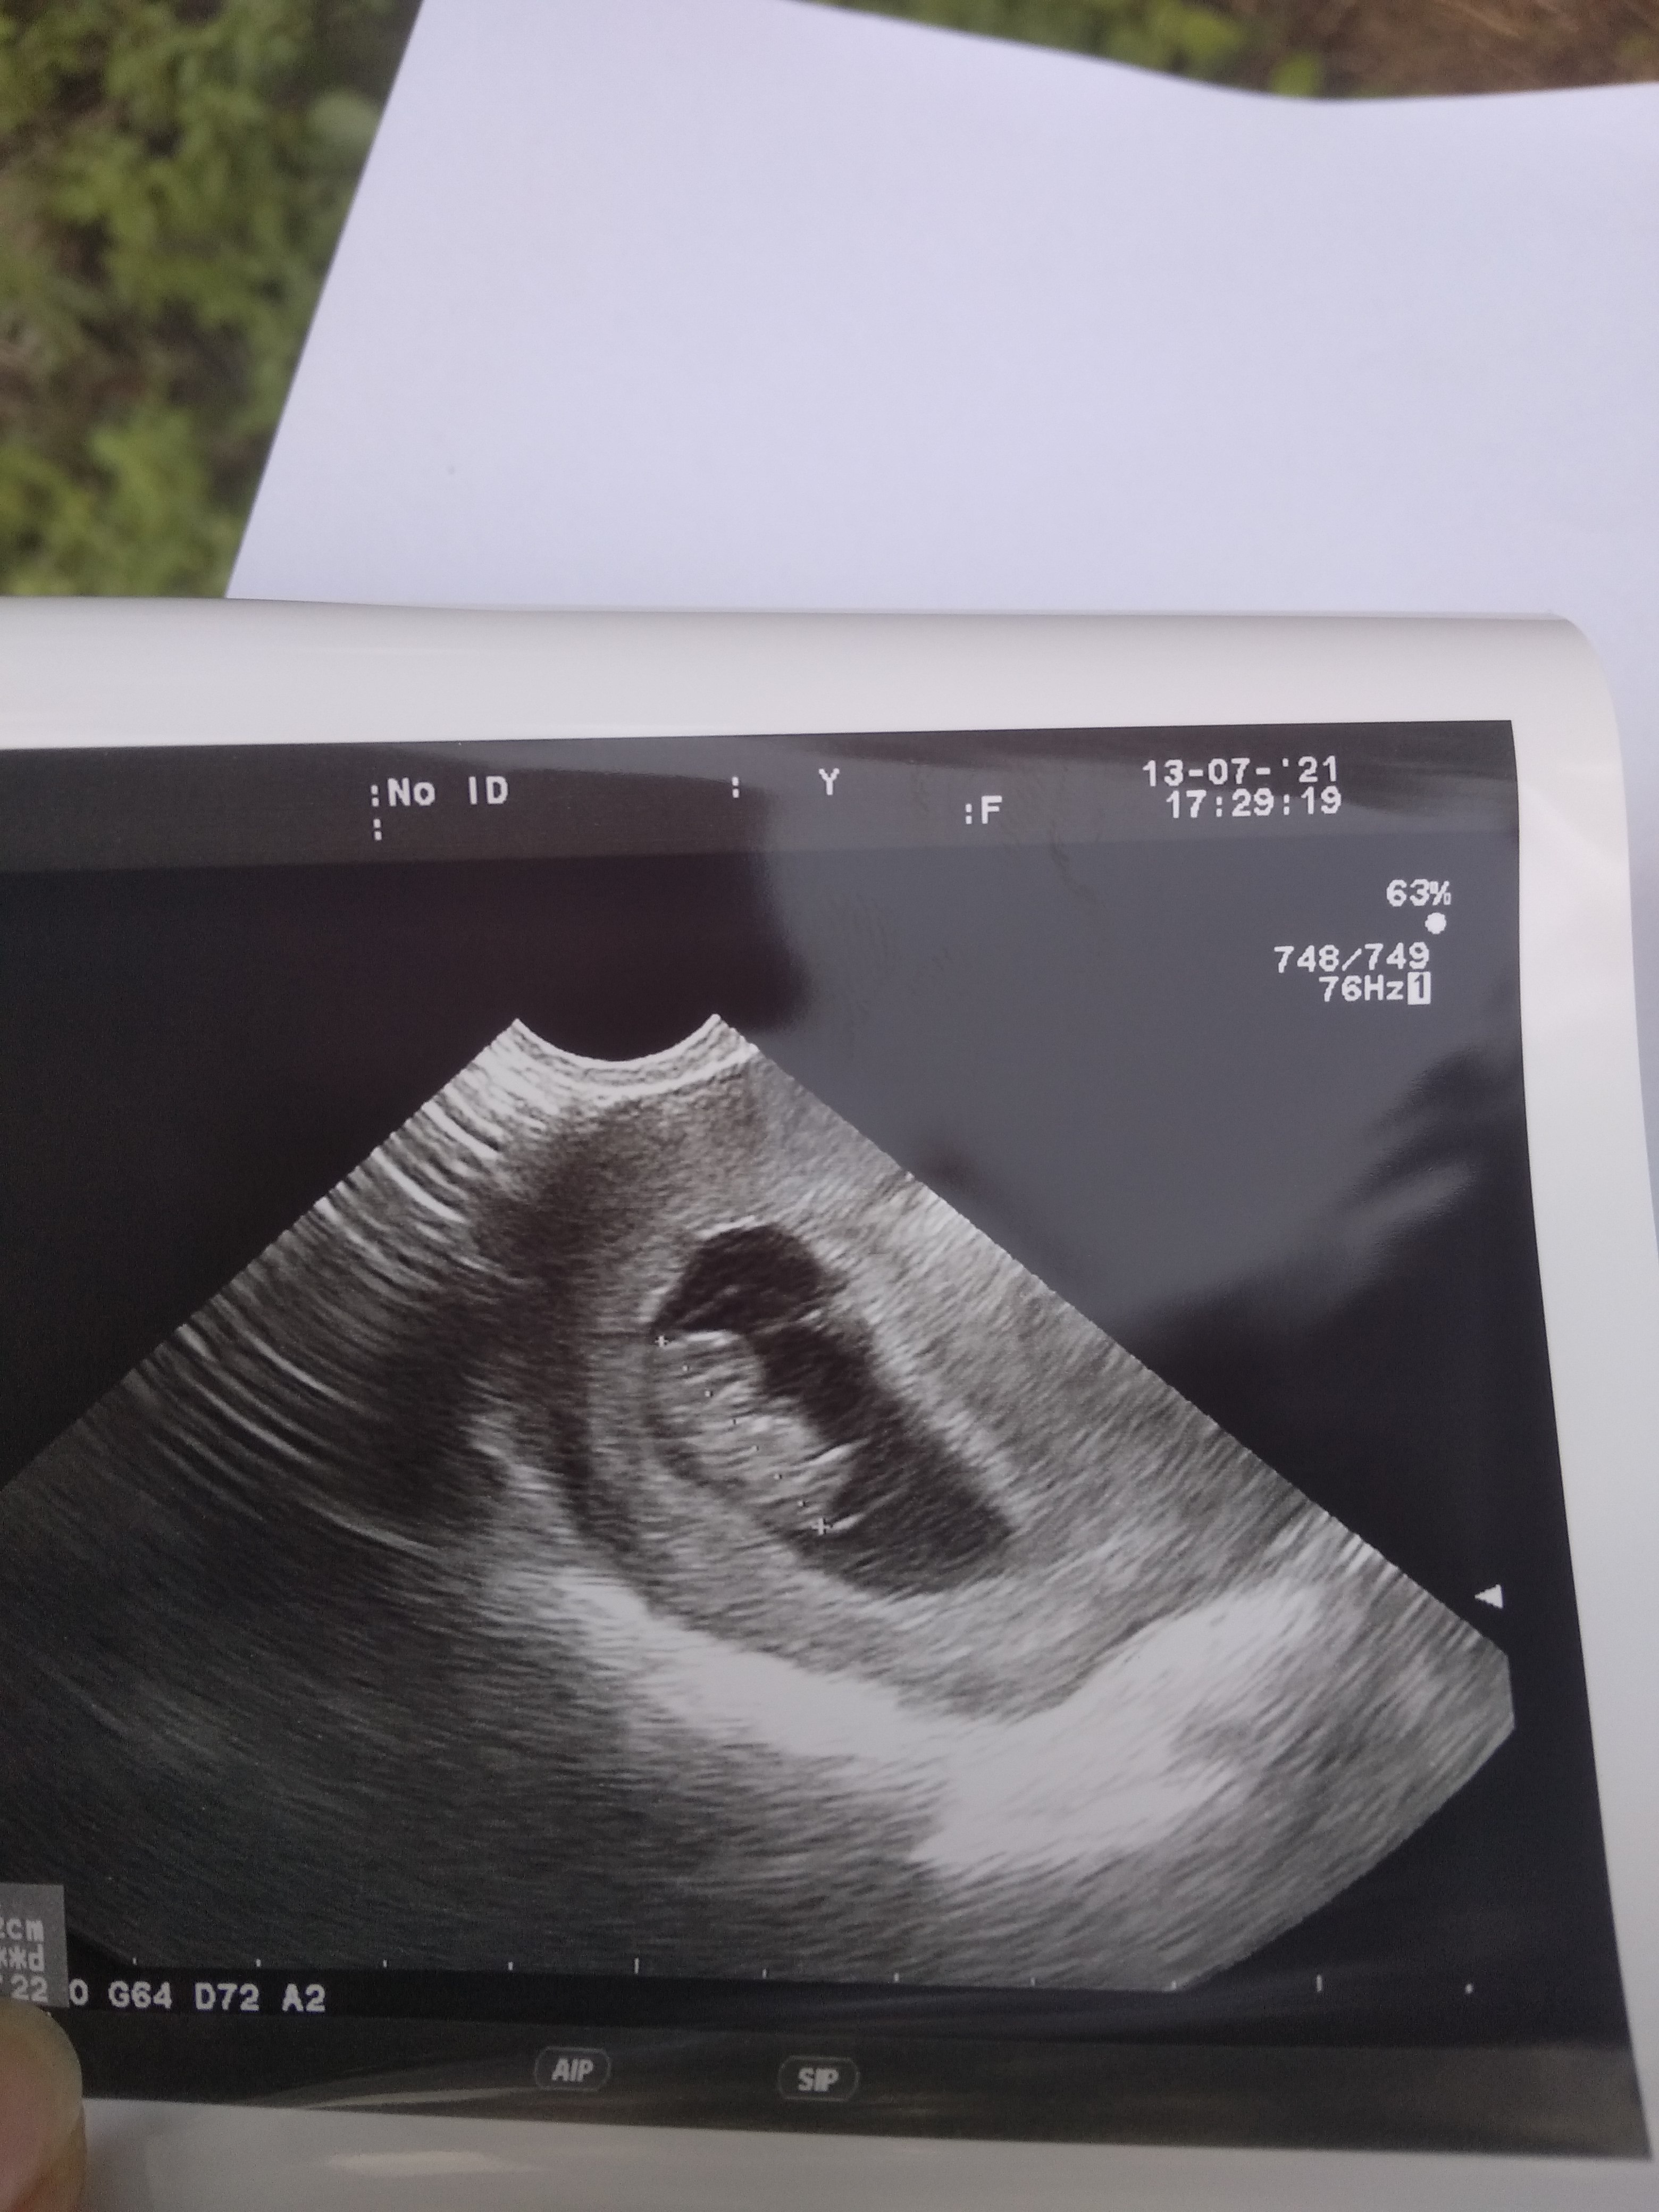

Tylko ilość uderzeń, powiedział, że za szybie tętno. Wszystko inne książkowe, dzidzius rośnie prawidłowo.Ja miałam 177 i lekarz powiedział że w porządku. Chodziło tylko o ilość uderzeń na min. czy jeszcze coś go zaniepokoiło że dał skierowanie?